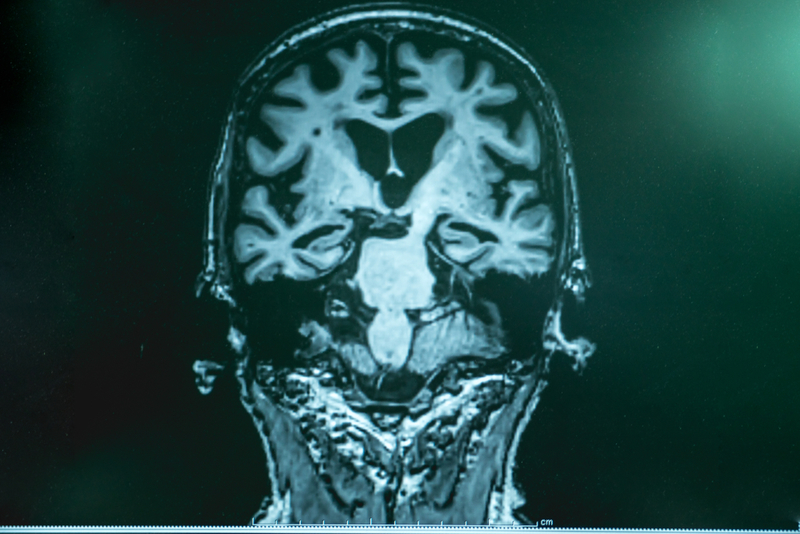

Micro doses of lithium can halt advanced Alzheimer, recover cognitive abilities, study finds

A study conducted by a team of researchers have found that lithium in doses up to 400 times lower than what is been prescribed for mood disorders is capable of halting signs of advanced Alzheimer's pathology and recovering of lost cognitive abilities.

The study was conducted by McGill researchers', led by Dr. Claudio Cuello of the Department of Pharmacology and Therapeutics, has shown that when given in a formulation that facilitates passage to brain, lithium prescribed in doses a few times lower than usually given can bring a halt to Alzheimer's disease. The finding is published in the latest edition of the Journal of Alzheimer's Disease.

Eventually, a new lithium formulation was then applied to rats that develop features of human Alzheimer's disease. The same lithium formulation at later stages of the disease to their transgenic rat modelling neuropathological aspects of Alzheimer's disease. This study found beneficial outcomes in diminishing pathology and improving cognition. After the practical research, the researchers came to a conclusion that microdoses of lithium in formulations, that facilitates passage to the brain through the brain-blood barrier while minimizing levels of lithium in the blood, sparing individuals from adverse effects, should find immediate therapeutic applications.

Dr. Cuello said: "While it is unlikely that any medication will revert the irreversible brain damage at the clinical stages of Alzheimer's it is very likely that treatment with microdoses of encapsulated lithium should have tangible beneficial effects at early, preclinical stages of the disease." Dr. Cuello is hopeful of finding, medical, industrial or financial partners for an effective treatment for those suffering from Alzheimer's disease.